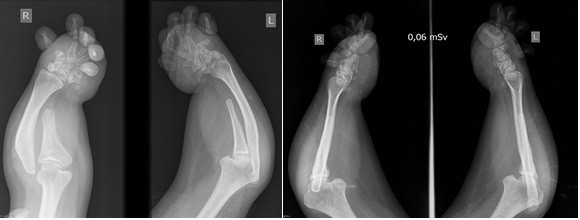

La condrodisplasia de Grebe es un trastorno raro autosómico recesivo que pertenece al grupo de las osteocondrodisplasias. Clínicamente se caracteriza por un severo dismorfismo con una marcada micromelia y deformidad de las extremidades inferiores y superiores. Conocer este tipo de síndrome orienta a dar mejores diagnósticos y permite el diagnóstico diferencial con patologías más comunes, como la acondroplasia. Se presenta una paciente de 35 años con diagnóstico de síndrome de Grebe desde los 10 años. El síndrome de Grebe tiene una muy baja incidencia; por este motivo, es poco conocido por el cuerpo médico en general y aun menos para los ortopedistas, quienes serán los encargados de tratar a estos pacientes. AbstractGrebe syndrome is a rare autosomal recessive disorder that belongs to the group of osteochondrodysplasias. Clinically, it is characterized by severe dysmorphism, marked micromelia and deformities of the lower and upper limbs. Recognition of this syndrome allows to give better diagnoses and to establish a differential diagnosis with more common pathologies, such as achondroplasia. We present a 35-year-old woman with diagnosis of Grebe syndrome at the age of 10. Grebe syndrome has a very low incidence; therefore, it is unknown by general physicians and still less by orthopedic surgeons, who will treat these patients.Descargas